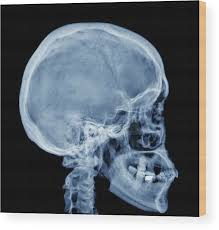

When I look up "normal human skull x-ray" things like this pop up.

I think that if someone was looking at this from an aesthetic POV then they would say that this is either recessed or downward grown, especially the midface area, because it doesn't look super projected when you compare it to man-made replicas.

When I look up "normal human skull x-ray" things like this pop up.

I think that if someone was looking at this from an aesthetic POV then they would say that this is either recessed or downward grown, especially the midface area, because it doesn't look super projected when you compare it to man-made replicas.